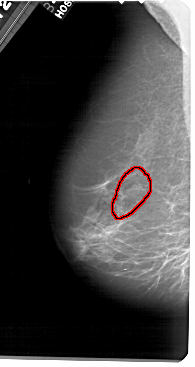

A_1651_1.RIGHT_CC

RIGHT_CC LINES 5056 PIXELS_PER_LINE 2836 BITS_PER_PIXEL 12 RESOLUTION 43.5 NON_OVERLAY

FILE: A_1651_1.LEFT_CC.OVERLAY

TOTAL_ABNORMALITIES 1

ABNORMALITY 1

LESION_TYPE CALCIFICATION TYPE PLEOMORPHIC DISTRIBUTION LINEAR

ASSESSMENT 4

SUBTLETY 1

PATHOLOGY BENIGN

TOTAL_OUTLINES 1

BOUNDARY